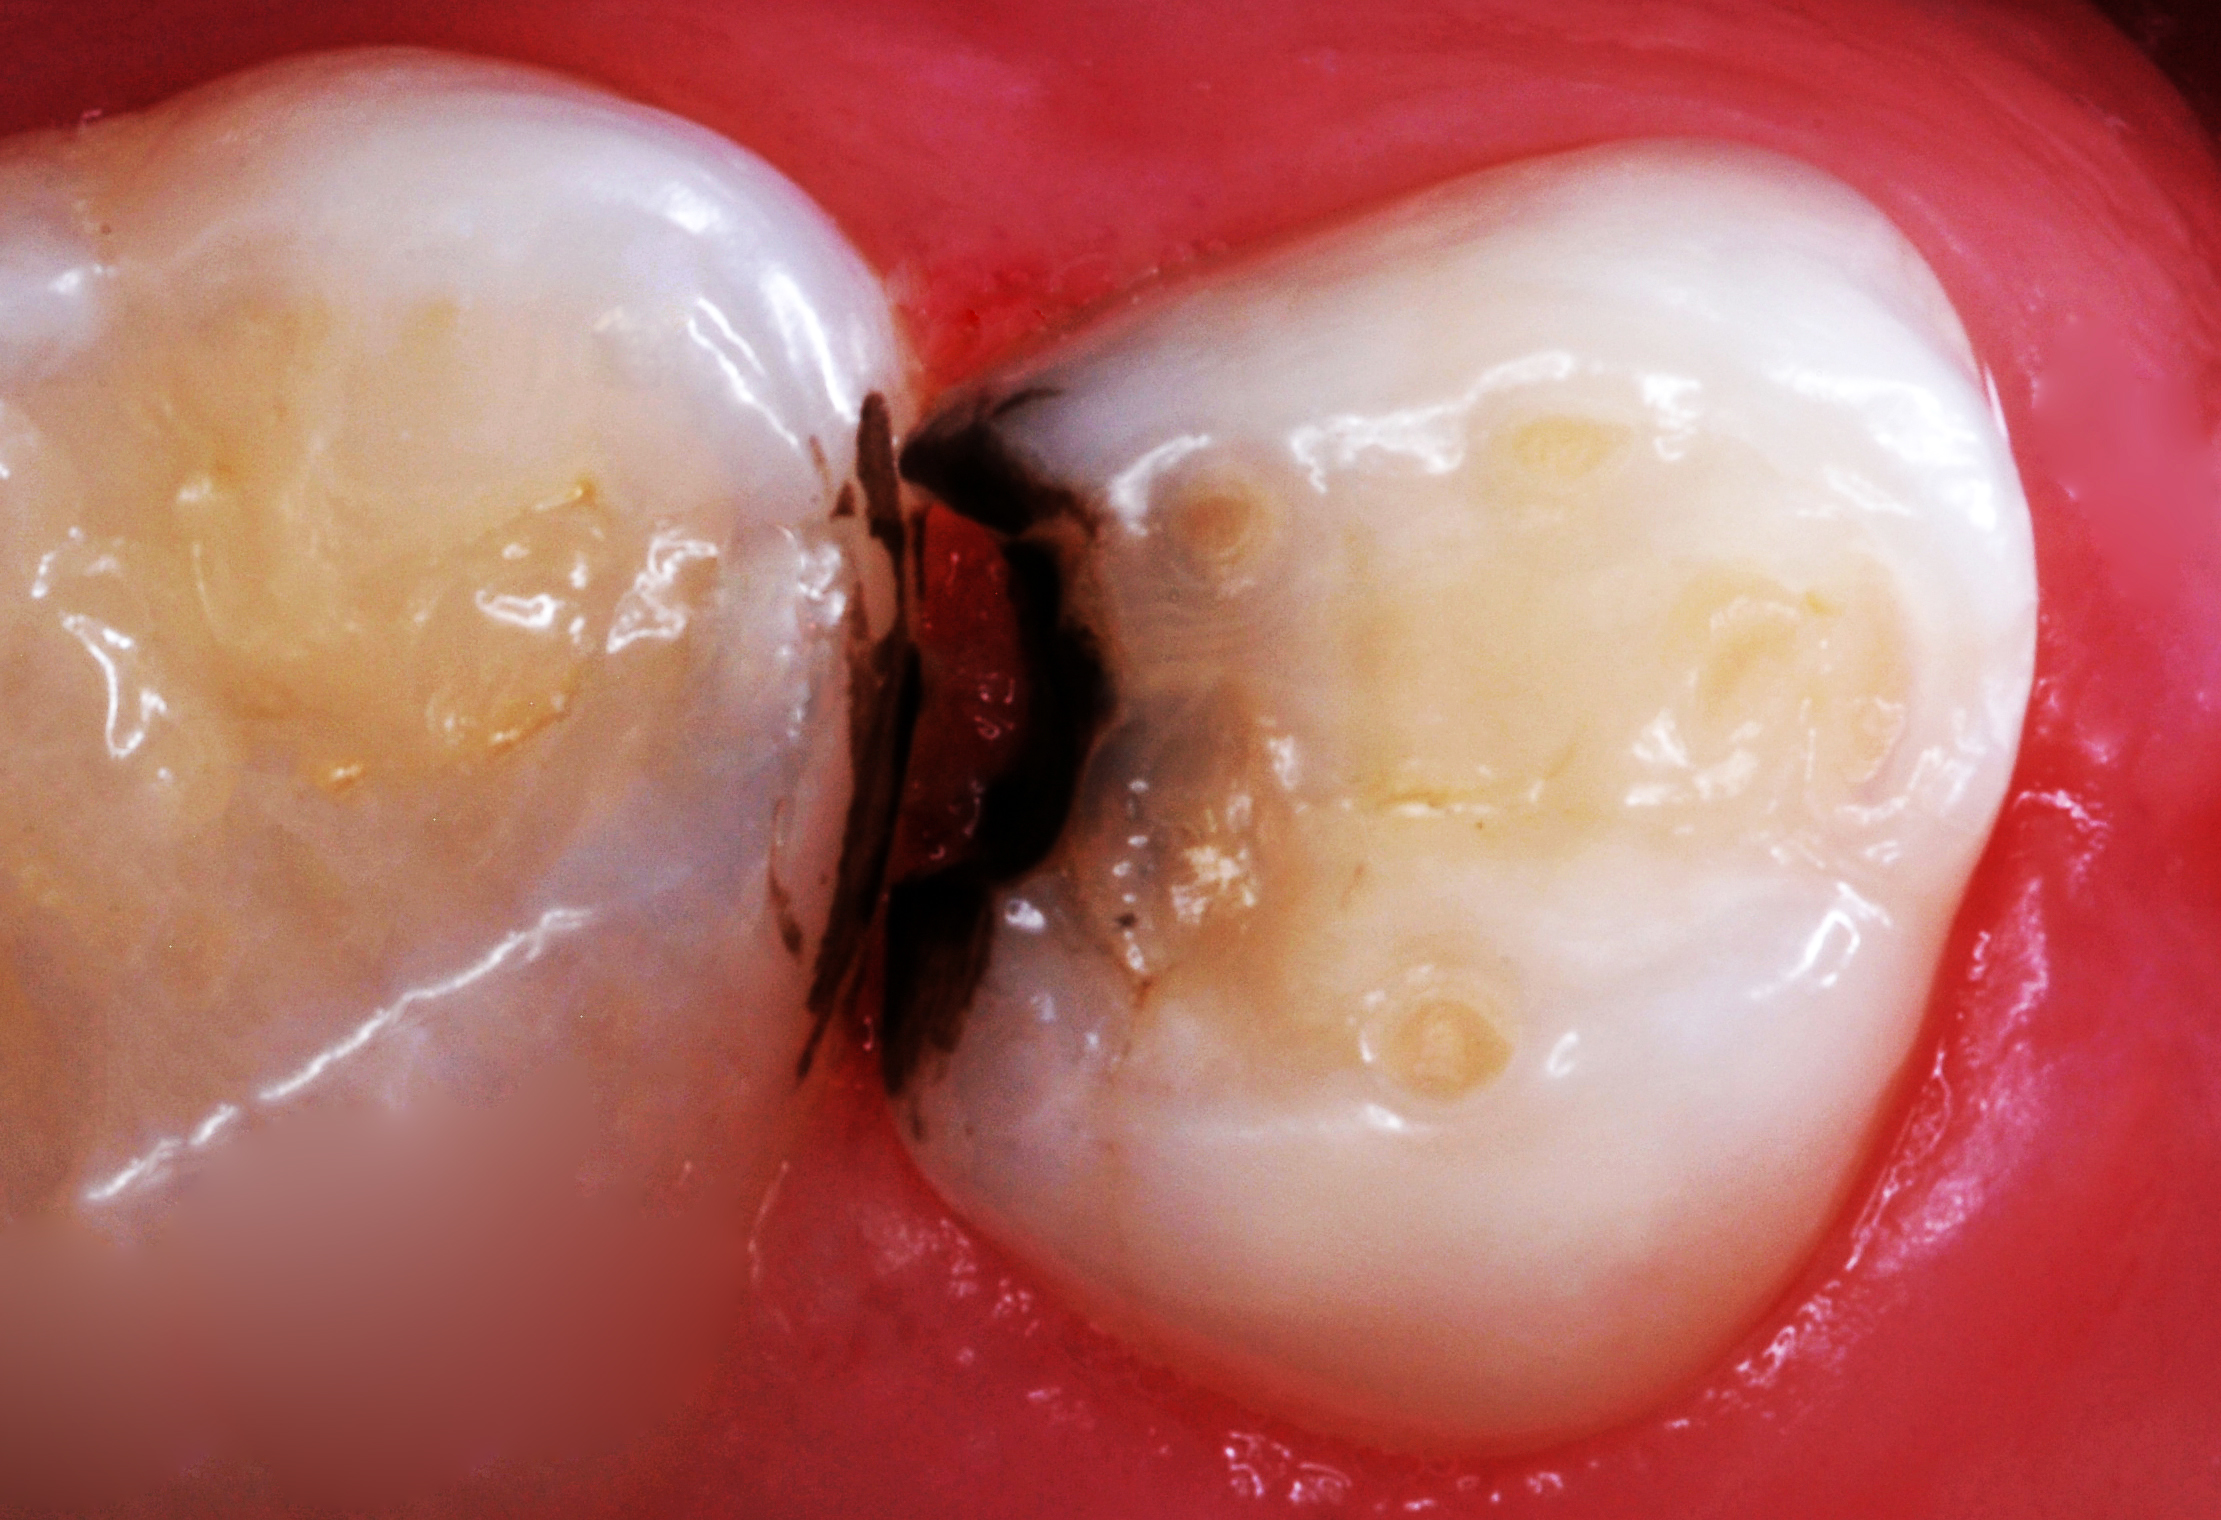

(8.) After exposure of disto-occlusal caries, SDF is applied, followed by a coating of fluoride varnish.

Figure 8

(9.) After exposure of disto-occlusal caries, SDF is applied, followed by a coating of fluoride varnish.

Figure 9